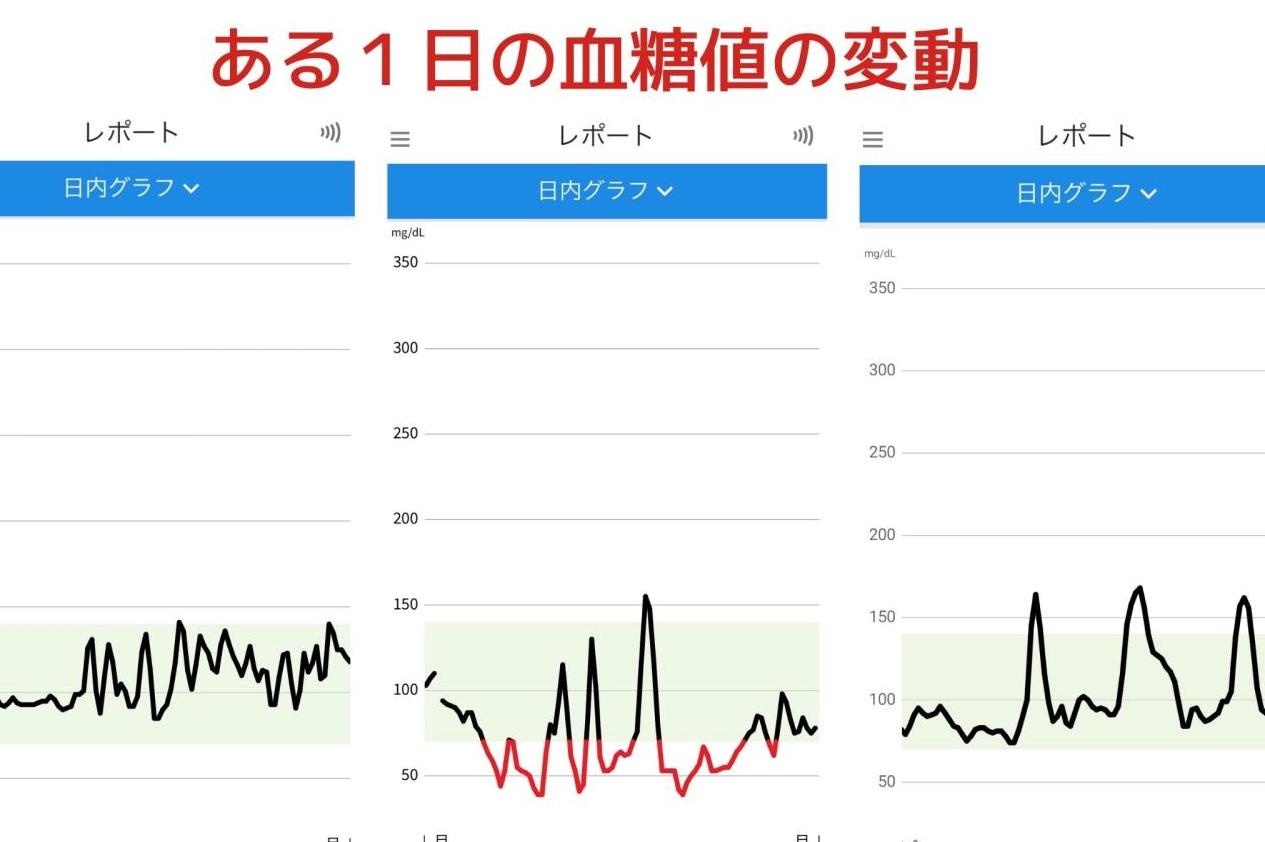

40代、50代が病気にならないための「血糖値ケア3カ条」2025.07.03

40代、50代が病気にならないための「血糖値ケア3カ条」2025.07.03 -